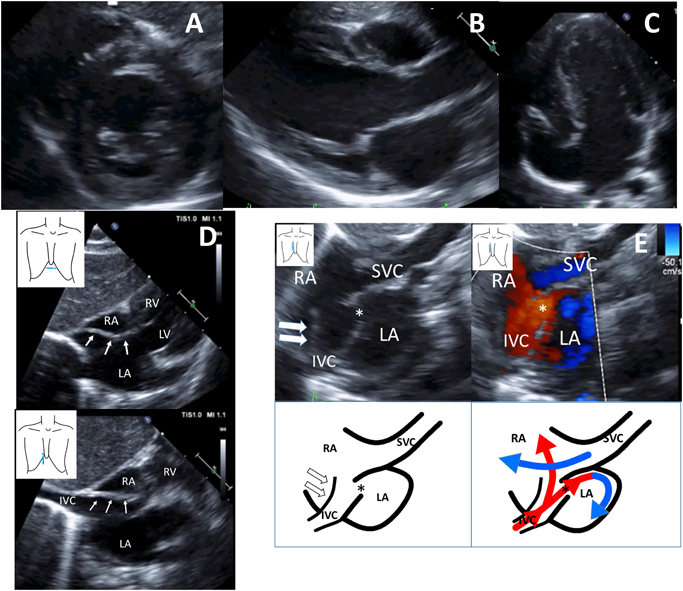

Using two-dimensional transthoracic echocardiography, we diagnosed the neonate with congenital tricuspid valve stenosis with a hypoplastic RV at first (Fig. 1A–C) and continued administering prostaglandin E1 infusion. The tricuspid valve was hypoplastic and dysplastic with trivial tricuspid regurgitation (the annulus measured 6.0 mm; the normal range is 9.3–17.5 mm; z-value, −3.9). The inflow of the tricuspid valve appeared to be substantially narrowed with an eccentric jet crossing from the RA to the hypoplastic RV. A pulse-wave Doppler ultrasound examination of the tricuspid valve’s inflow revealed it had a monophasic pattern with maximal velocities of 1.4 m/s. The pulmonary valve’s annulus was smaller (6.6 mm; the normal range is 5.9–9.8 mm; Z-value −0.93), but there was no evidence of abnormal valve thickening or flow acceleration and valve regurgitation on color or pulsed Doppler ultrasound examinations.

Fig. 1 LV short axis (A), LV long axis (B), and apical four chamber (C) two-dimensional echocardiography views showing a hypoplastic RV and the tricuspid valve diameter (6.0 mm, Z value −3.9) after birth (D) Subxiphoid coronal and sagittal two-dimensional echocardiography views showing a linear membranous structure projecting into the RA arising from the junction of the IVC. (E)Right sternal border sagittal two-dimensional echocardiography view showing a linear membranous structure projecting into the RA and PFO, and anterior deviation of the atrial secondum septum. Color Doppler image showing a linear membranous structure that hemodynamically divided the RA into two chambers. The flow from the IVC was partially redirected into the LA via the PFO and flow from the SVC mainly drained into the RA.

IVC, inferior vena cava; LA, left atrium; LV, left ventricle; PFO, patent foramen ovale; RA,right atrium; RV, right ventricle; SVC, superior vena cava. white arrow: membranous structure. * PFO

A few days later, we noticed there was a prominent and elongated membranous structure extending from the junction of the IVC to the RA (Fig. 1D). Color Doppler ultrasound with a right sternal border sagittal view showed that the large membranous structure hemodynamically divided the RA into two chambers; that is, both blood flow from the IVC and superior vena cava (SVC) were partially redirected by this membrane to the LA via the PFO, leading us to diagnose the patient with CTD (Fig. 1E). After stopping prostaglandin E1 infusion, we confirmed that the ductus arteriosus was closed, and the patient’s saturation values remained at approximately 85%–93% with oxygen inhalation (1 L/min nasal cannula).